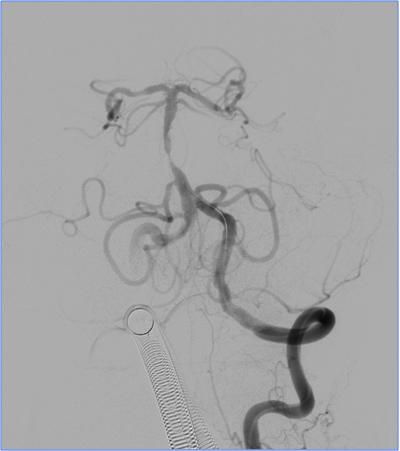

▼13:49DSA

▼支架取栓后基底动脉残余重度狭窄

▼基底动脉支架置入术

▼4天后复查MRA

》DSA见基底动脉闭塞,Solitaire支架取栓后见基底动脉重度狭窄,Gateway球囊扩张,置入Wingspan支架。

》术后24h完全恢复,NIHSS评分0分。